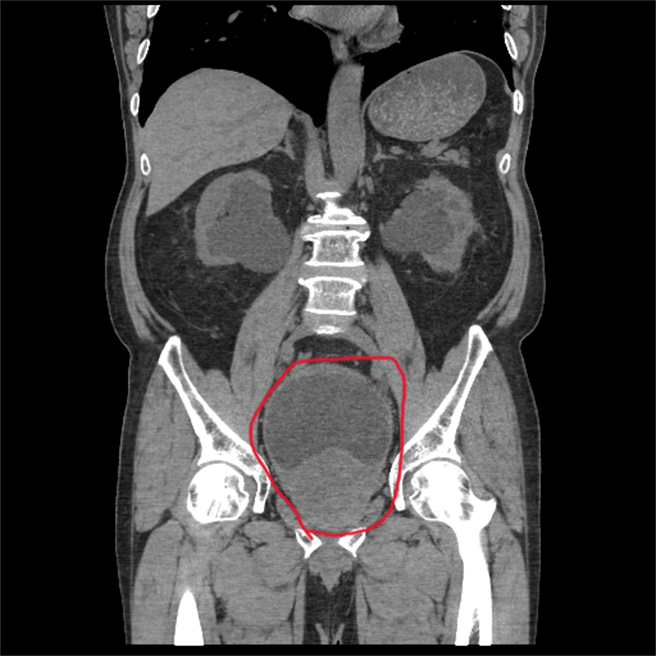

泌尿外科呂謹亨醫師呂謹亨指出,陳男因攝護腺肥大,尿液無法順利排出,經問診發現陳男每次都尿不乾淨,導致膀胱壁逐漸變粗、變厚,但他長期置之不理,經治療排出約1500 cc的尿液,再手術刮除攝護腺,3天就出院,成功保住腎臟。

泌尿外科呂謹亨醫師呂謹亨指出,陳男因攝護腺肥大,尿液無法順利排出,經問診發現陳男每次都尿不乾淨,導致膀胱壁逐漸變粗、變厚。(員榮醫院提供/吳建輝彰化傳真)